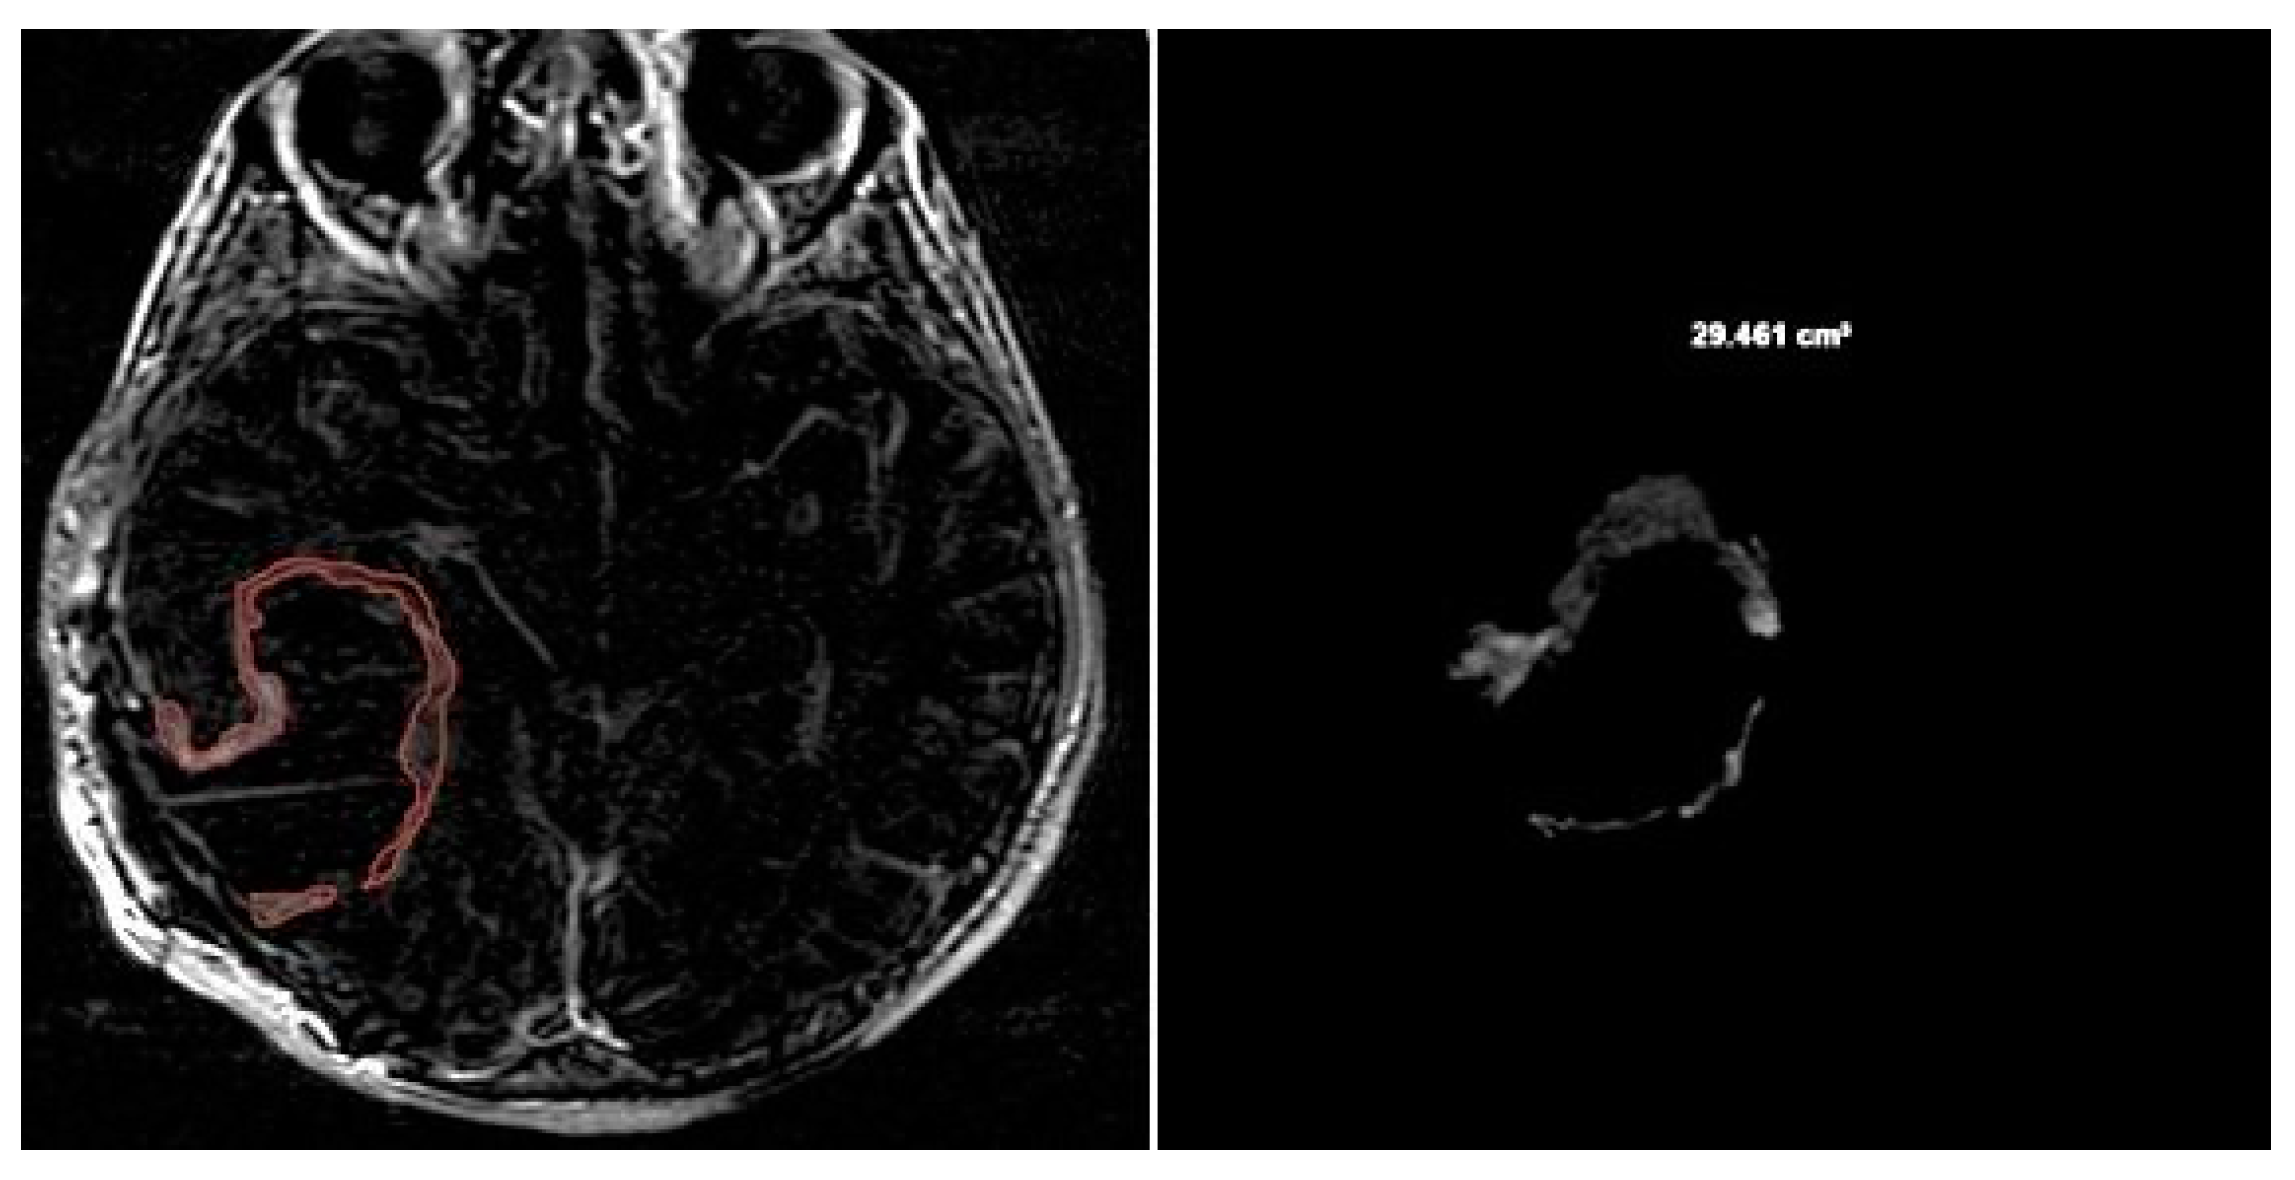

CE-RTV was assessed on 2D axial CE-T1w images (slice thickness: 5 mm.; slice spacing: 5,5-6 mm.), achieved with subtraction imaging technique to minimize errors due to the spontaneous hyperintensity of degradation products of hemoglobin or related to the presence of haemostatic/chemotherapeutic agents in the surgical area. As for CE-PTV, the analysis was performed both manually and semi-automatically [Figure 3 and Figure 4].

Figure 3. Contrast Enhancement Postoperative Tumor Volume (CE-RTV) manual evaluation.

Preprints 86216 g003

Figure 4. Contrast Enhancement Postoperative Tumor Volume (CE-RTV) semi-automatic evaluation.